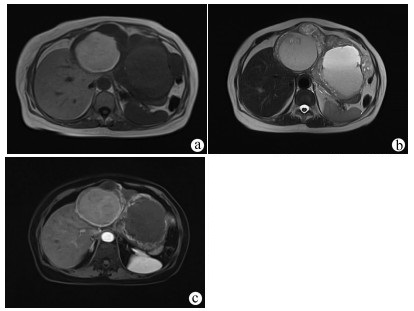

Recurrence after hepatectomy for primary gastrointestinal stromal tumor of the liver: A case report

Kangwei LIU, Xin GENG, Lei WANG, Cijun PENG

2021, 37(12): 2893-2895. DOI: 10.3969/j.issn.1001-5256.2021.12.031

Abstract(971) HTML (239) PDF (2357KB)(56)

Abstract: